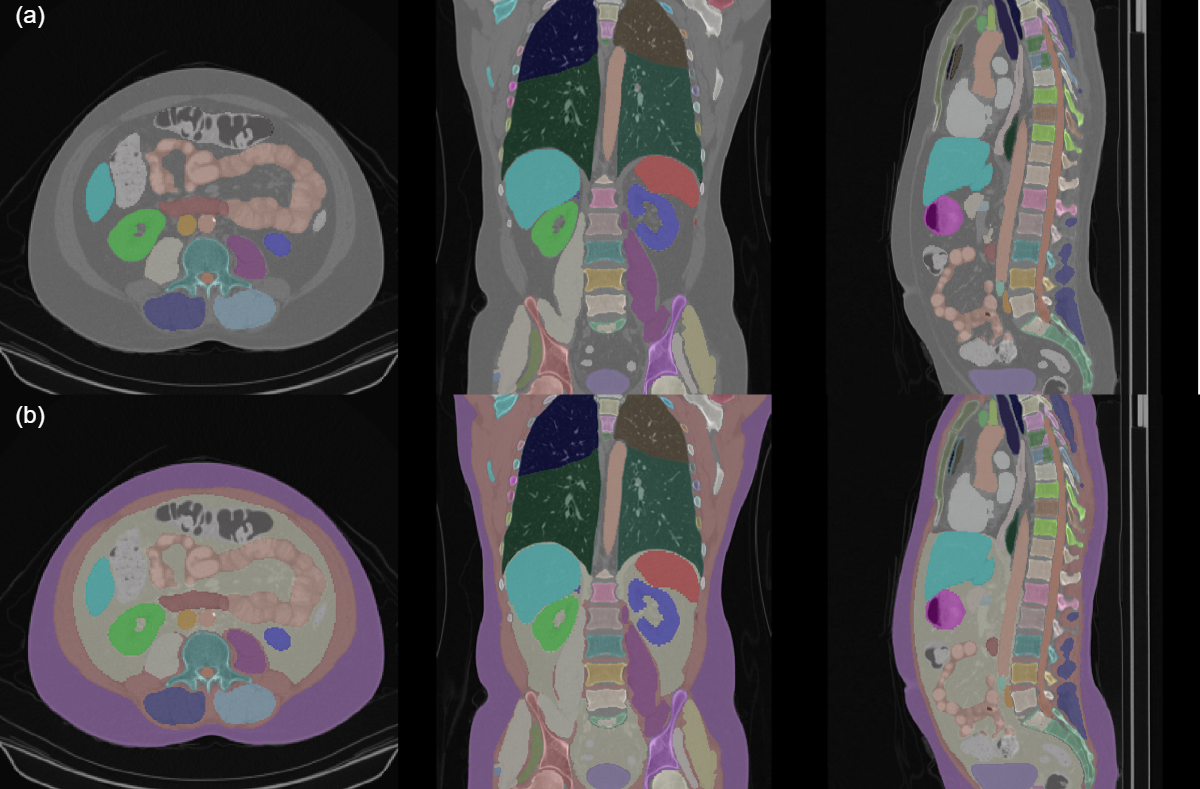

Refer to caption

Figure 2: (a) An example of the TotalSegmentator dataset for a coronal, axial, and sagittal view of a thoracic/abdominal CT scan. (b) An example of the combined SAROS predictions and TotalSegmentator ground-truth.

We initially trained a U-Mamba model on the SAROS dataset to make predictions on the TotalSegmentator dataset. These predictions were merged with the TotalSegmentator ground-truth masks, prioritising the ground-truth where they overlap, to build a richly annotated dataset incorporating SAT and abdominal cavity pseudo ground-truth, for training a single model. Fig. 2 shows an example of this process. We then trained a U-Mamba model on the combined dataset. As shown in Fig. 1, KEVS then accurately segments both SAT and an organ-free abdominal cavity.